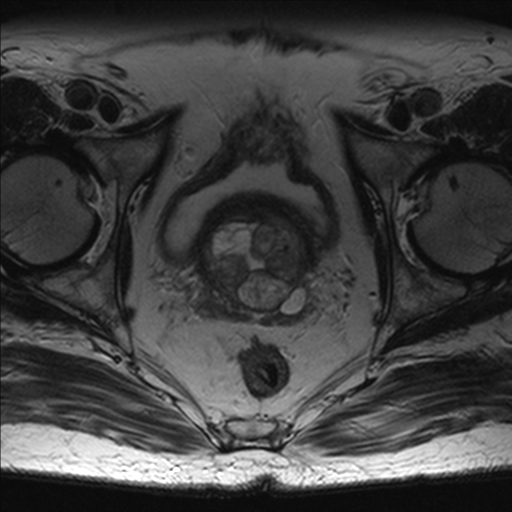

RM Pelvis

Prueba diagnóstica no invasiva que consiste en la obtención de imágenes de alta definición anatómica de la pelvis mediante el empleo de un campo electromagnético y ondas de radio (con un emisor y un receptor). No utiliza radiación ionizante. Se realiza para estudiar patologías del útero, del ovario, de las trompas y la vagina, ya sean de origen tumoral, inflamatorio o vascular. Esta prueba permite valorar órganos como la vejiga urinaria, la unión entre los uréteres y la vejiga, la próstata, las vesículas seminales, la uretra, los huesos de la pelvis, etc A veces requiere el uso de contraste intravenoso (Gadolinio) para caracterizar las lesiones.